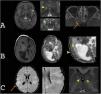

Macrocephaly is a clinical term defined as an occipitofrontal circumference more than two standard deviations above the mean. It is present in 5% of children and is a common indication for imaging studies. There are multiple causes of macrocephaly; most of them are benign. Nevertheless, in some cases, macrocephaly is the clinical manifestation of a condition that requires timely medical and/or surgical treatment. The importance of imaging studies lies in identifying the patients who would benefit from treatment. Children with macrocephaly associated with neurologic alterations, neurocutaneous stigmata, delayed development, or rapid increase of the circumference have a greater risk of having disease. By contrast, parental macrocephaly is predictive of a benign condition. Limiting imaging studies to patients with increased risk makes it possible to optimize resources and reduce unnecessary exposure to tests.